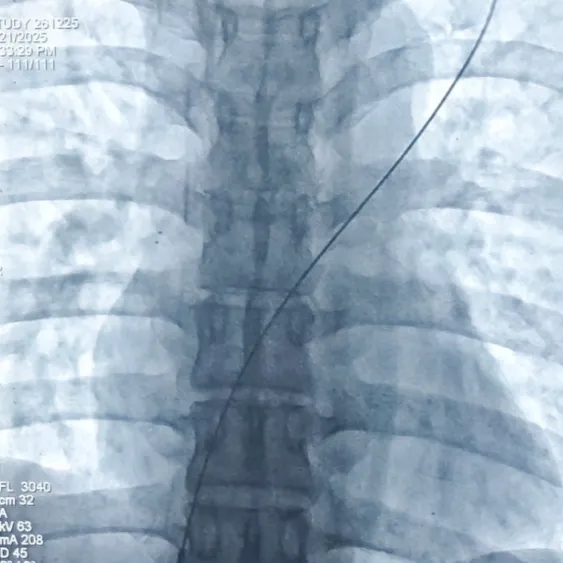

导丝过隔

送入输送鞘,撤出导丝